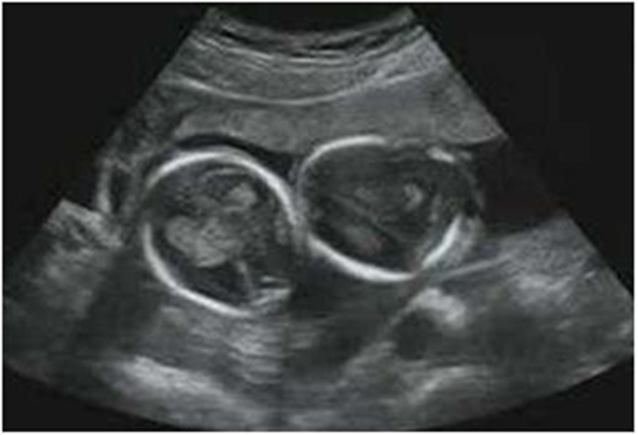

In early ultrasound before week 11, two yolk vesicles can be seen, although early diagnosis of amnionicity from the number of yolk vesicles is not always accurate Figure 11.

Figure 11 Biamniotic bicorial gestation, the two yolk sacs are observed.